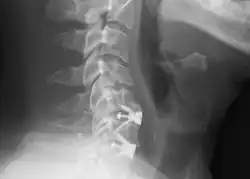

![]() X-rays of anterior cervical discectomy and fusion, C5C6 and C6C7. Lateral view. | |